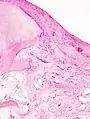

- Histopathology of osteoarthrosis of a knee joint in an elderly female.